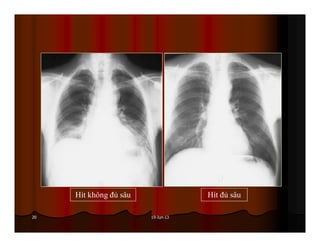

Được xem là hít đủ sâu khi ta thấy được hình chiếu của xương

sườn lên phổi 6 cung sườn trước hoặc 10 cung sườn sau.

Hít không đủ sâu Hít đủ sâu